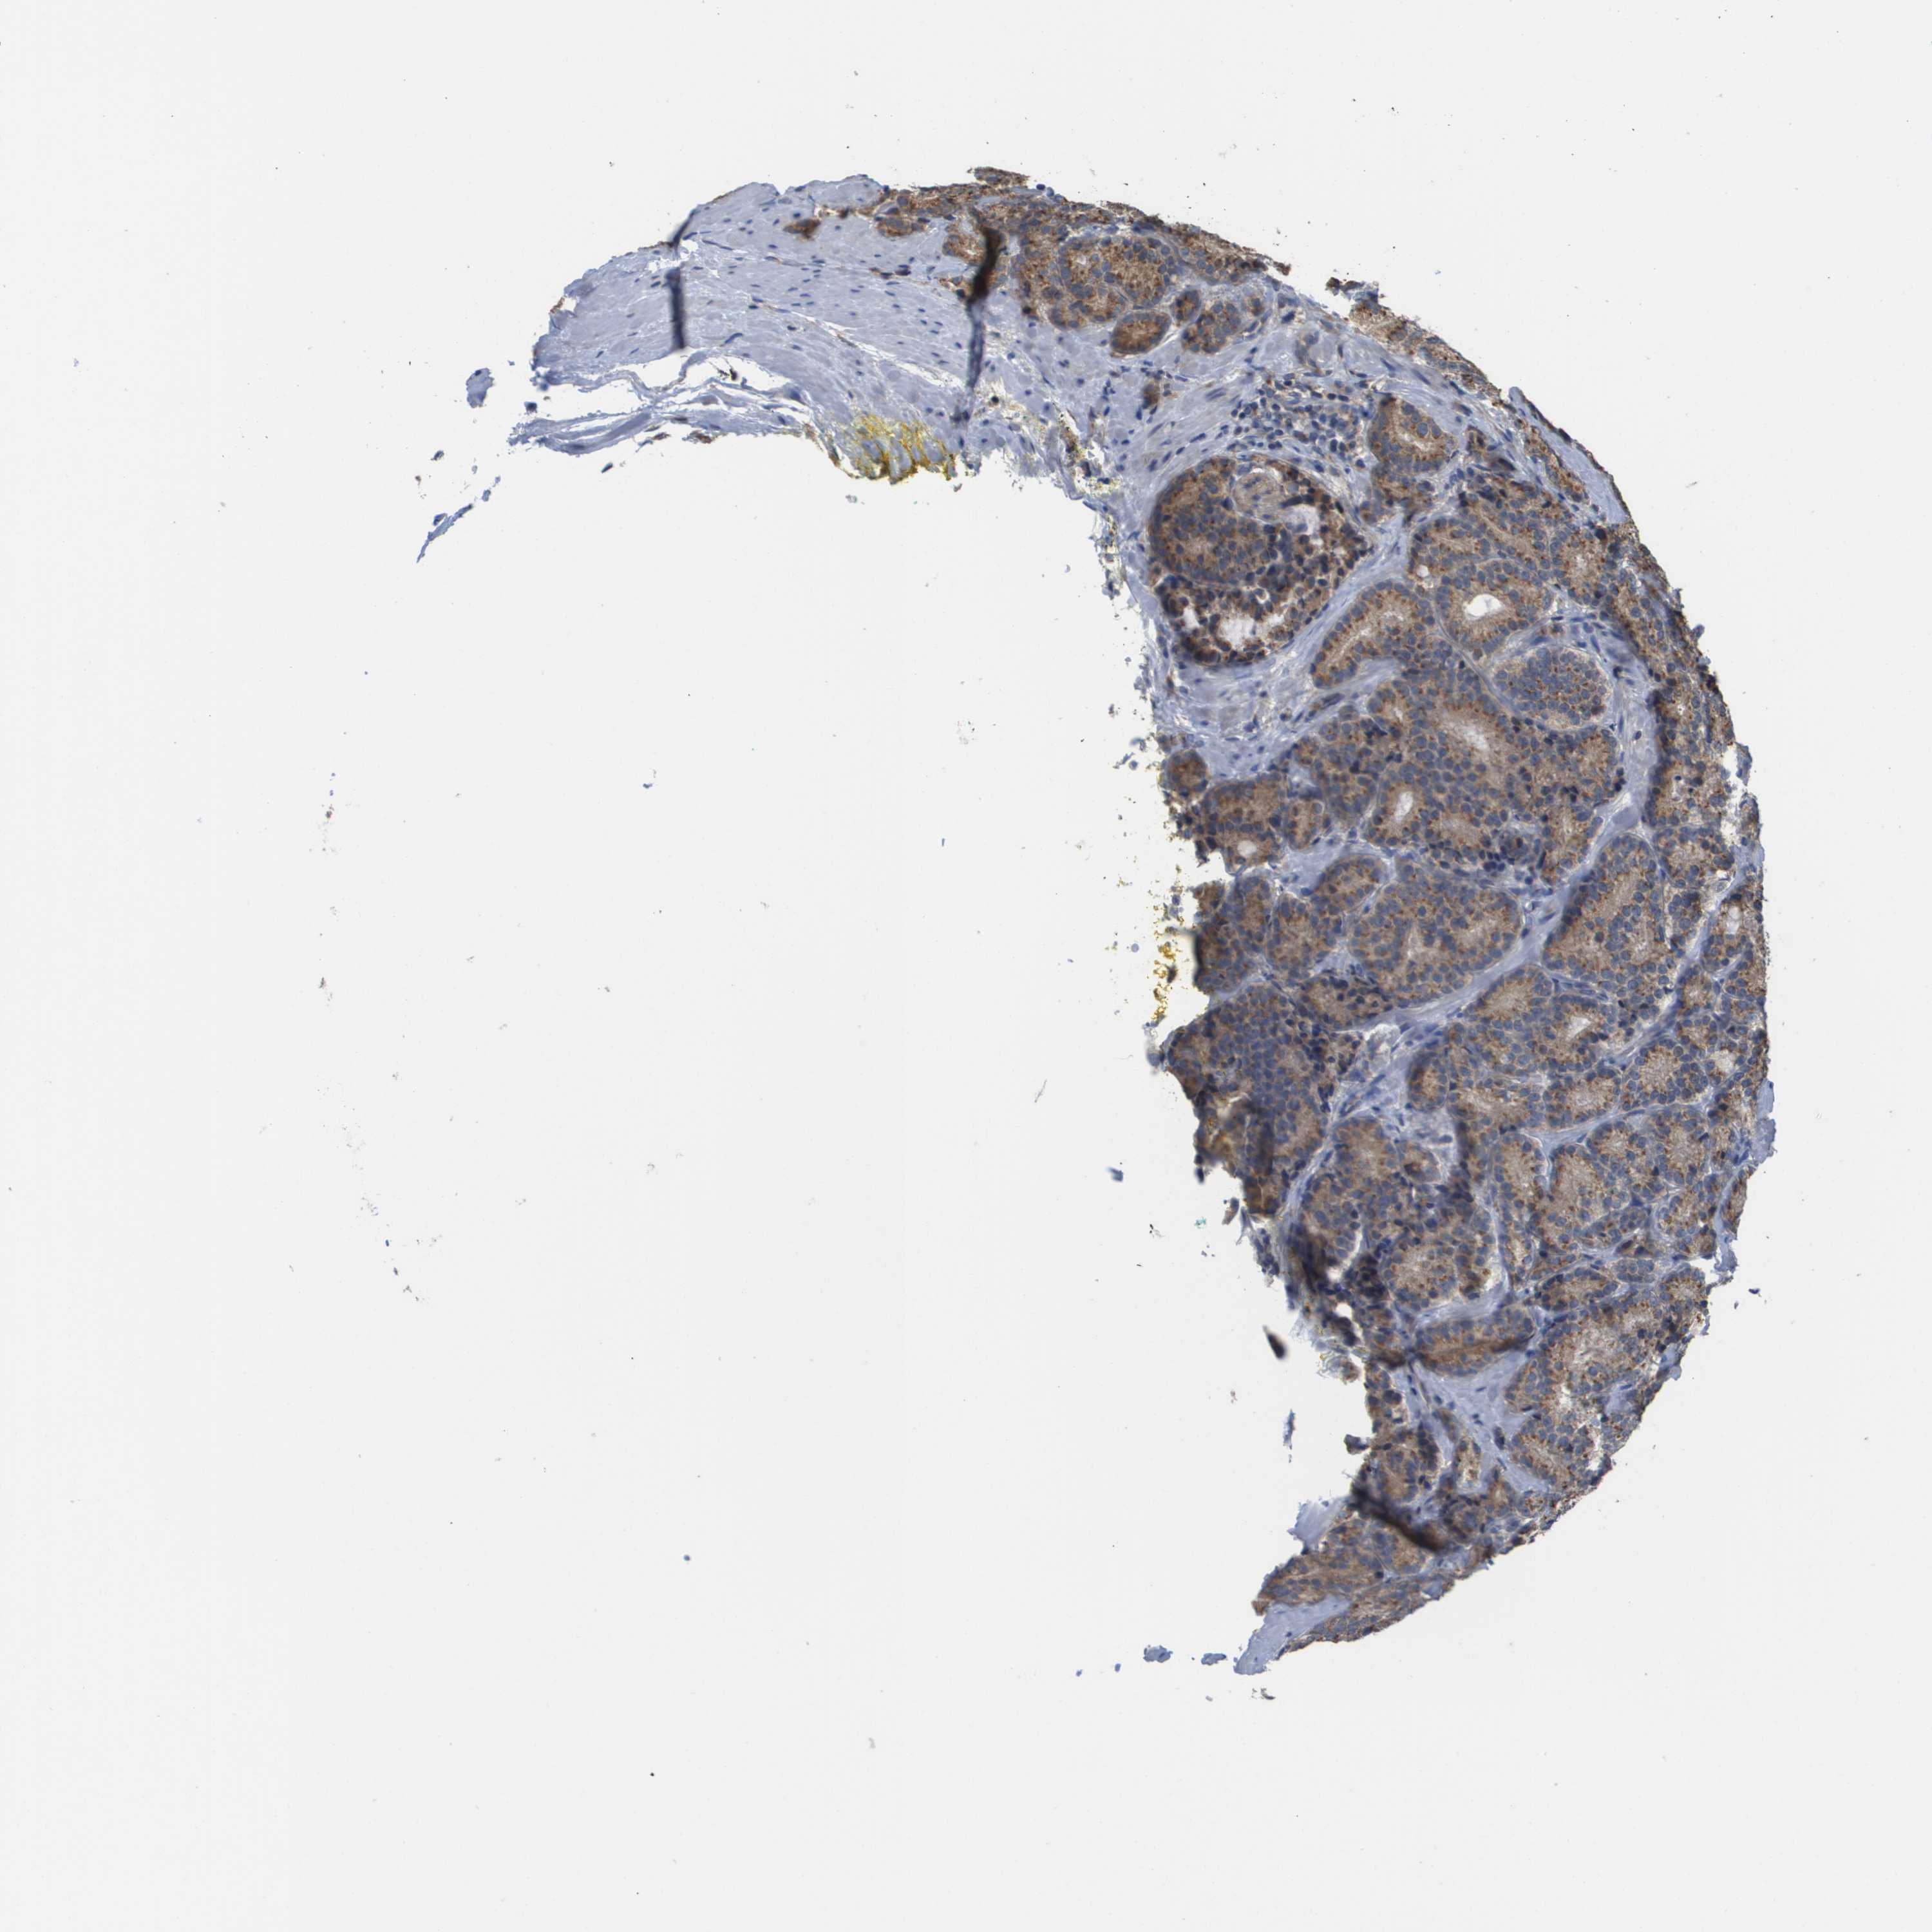

PROSTATE CANCER - Protein expressioni

A mouse-over function shows sample information and annotation data. Click on an image to view it in a full screen mode. Samples can be filtered based on level of antibody staining by selecting one or several of the following categories: high, medium, low and not detected. The assay and annotation is described here.

Antibody stainingi

Antibody staining in the annotated cell types in the current human tissue is reported as not detected, low, medium, or high, based on conventional immunohistochemistry profiling in selected tissues. This score is based on the combination of the staining intensity and fraction of stained cells.

Each image is clickable and will lead to virtual microscopy that enables deeper exploration of all samples and also displays staining intensity scores, fraction scores and subcellular localization as well as patient and tissue information for each sample.

Antibody HPA006277

Antibody HPA006507

Antibody CAB017027

Staining

High

Medium

Low

Not detected

Intensity

Strong

Moderate

Weak

Negative

Quantity

>75%

75%-25%

<25%

None

Location

Nuclear

Cytoplasmic/membranous

Cytoplasmic/membranous,nuclear

Adenocarcinoma, High grade

Adenocarcinoma, Low grade